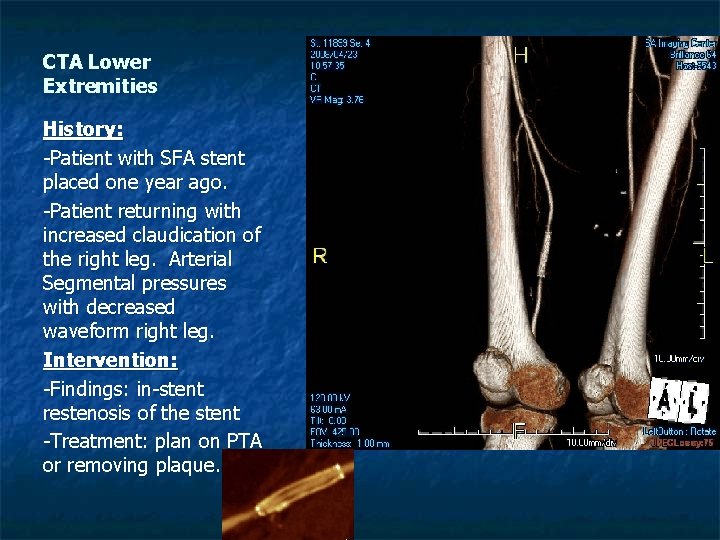

CTA Lower Extremities History: -Patient with SFA stent placed one year ago. -Patient returning with increased claudication of the right leg. Arterial Segmental pressures with decreased waveform right leg. Intervention: -Findings: in-stent restenosis of the stent -Treatment: plan on PTA or removing plaque.